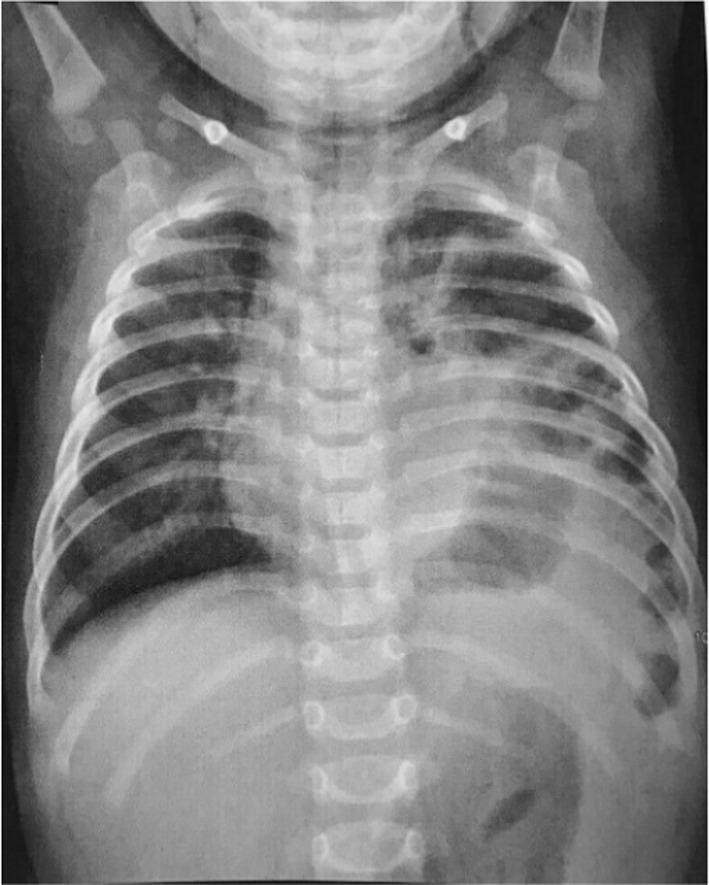

Bochdalek hernia is a rare condition characterized by the displacement of abdominal contents into the thoracic cavity. Due to the nonspecific nature of symptoms, prompt diagnosis, and management by emergency care providers can be challenging. Treatment of a Bochdalek hernia typically involves the reduction in the herniated contents back into the abdominal cavity. In this case report, we present the case of a 1-year-old girl who presented to the emergency department with a fever and bicytopenia. Further evaluation revealed a Bochdalek hernia, which was successfully managed with surgical intervention. This case highlights the importance of considering a Bochdalek hernia in the differential diagnosis of patients presenting with recurrent nonspecific symptoms (fever and bicytopenia).

博赫达勒克疝是一种罕见病症,其特征为腹腔内容物移位至胸腔。由于症状不具有特异性,急诊医护人员要做出快速诊断并进行处理颇具挑战性。博赫达勒克疝的治疗通常包括将疝出的内容物回纳至腹腔。在本病例报告中,我们呈现了一名1岁女童的病例,该女童因发热和双细胞减少症就诊于急诊科。进一步检查发现了博赫达勒克疝,通过手术干预成功治愈。该病例凸显了在对出现反复非特异性症状(发热和双细胞减少症)的患者进行鉴别诊断时考虑博赫达勒克疝的重要性。